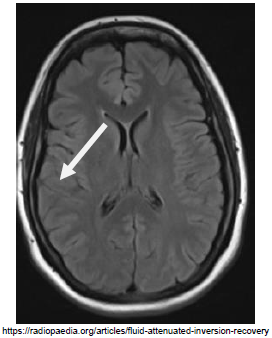

Sobre a imagem de ressonância magnética apresentada abaixo, assinale a afirmativa correta: